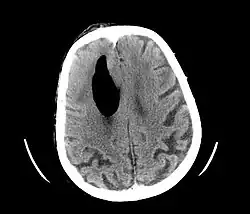

![]() Odma wewnątrzczaszkowa u pacjentki jako powikłanie pooperacyjne resekcji raka kolczystokomórkowego skóry głowy. | |

Odma wewnątrzczaszkowa, odma czaszkowa (łac. pneumocephalia, pneumoencephalon) – stan w którym dochodzi do dostania się powietrza do jamy czaszki, najczęściej wskutek złamania w obrębie podstawy czaszki lub sklepienia czaszki przebiegającego z rozerwaniem opony twardej, oczodołu[1], powikłań operacji neurochirurgicznych[2], lub operacyjnego leczenia wodogłowia[3].